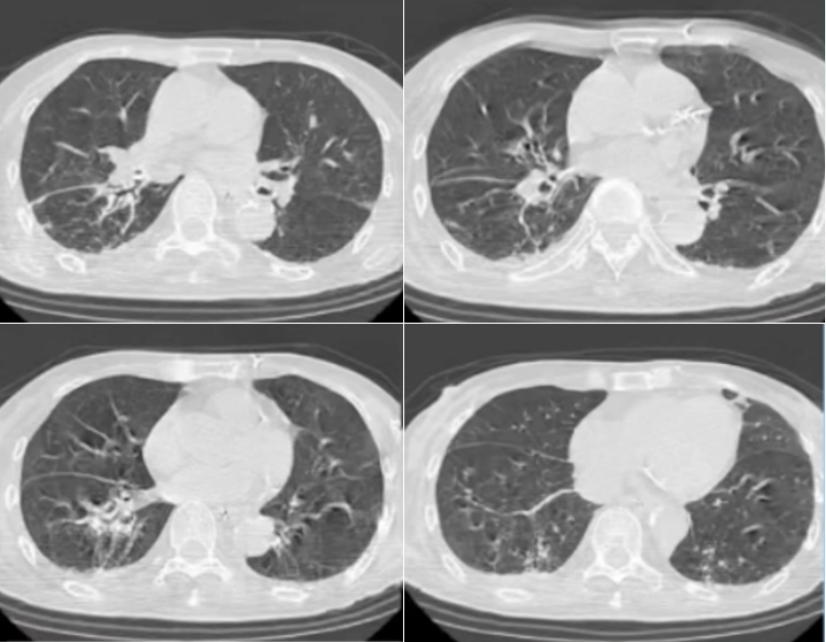

• 胸部CT:右肺下叶为主的炎性病变(图1)

1  患者入院后胸部CT(2024-07-04)

7月20日复查胸部CT:右肺下叶炎症较前明显吸收(图5)

5  复查胸部CT(2024-07-20)